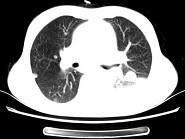

问题 女,55岁,胸痛伴咯血丝痰1周,胸部CT如图,最可能的诊断为 ( )

选项 A.转移性肺癌 B.左侧周围型肺癌并肺内转移 C.左侧中央型肺癌并肺内转移 D.多发性肺脓肿 E.结节病

答案 B